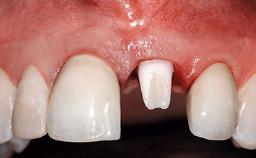

A 32-year-old female Caucasian patient with a compromised maxillary right central incisor was referred to us by a general dentist. Her chief complaints were discomfort and mobility of tooth 11 with unsatisfactory esthetics due to discoloration. The patient reported a previous trauma, some years earlier, as the origin of pathology on the afflicted tooth. Anamnesis was negative for any other dental or periodontal pathology in the remaining dentition. The patient did not take any medication and reported to be a light smoker (5–10 cigs/day). She had high esthetic expectations of her treatment. The extraoral examination revealed a high smile line with full exposure of her maxillary teeth and surrounding soft tissue in the area between the second premolars.

Defining Characteristics One missing tooth to be replaced by an implant-borne crown

Provisional Implant-Supported Prosthesis Prosthodontic margin > 3 mm apical to mucosal margin Prosthodontic margin > 3 mm apical to mucosal margin